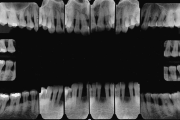

Krooniline parodontiit

Krooniline parodontiit on mikroobide poolt põhjustatud hammaste tugikudede põletik, mille tulemusena tekib progresseeruv alveolaarluu (nähtav röntgenograamil) ja periodontaalligamendi destruktsioon, igemetaskute moodustumine, igeme retsessioon või mõlemad kahjustused kombineeritult. Loe edasi »

- luu destruktsioon (5)

- vertikaalne luukadu (2)

- horisontaalne luukadu (3)